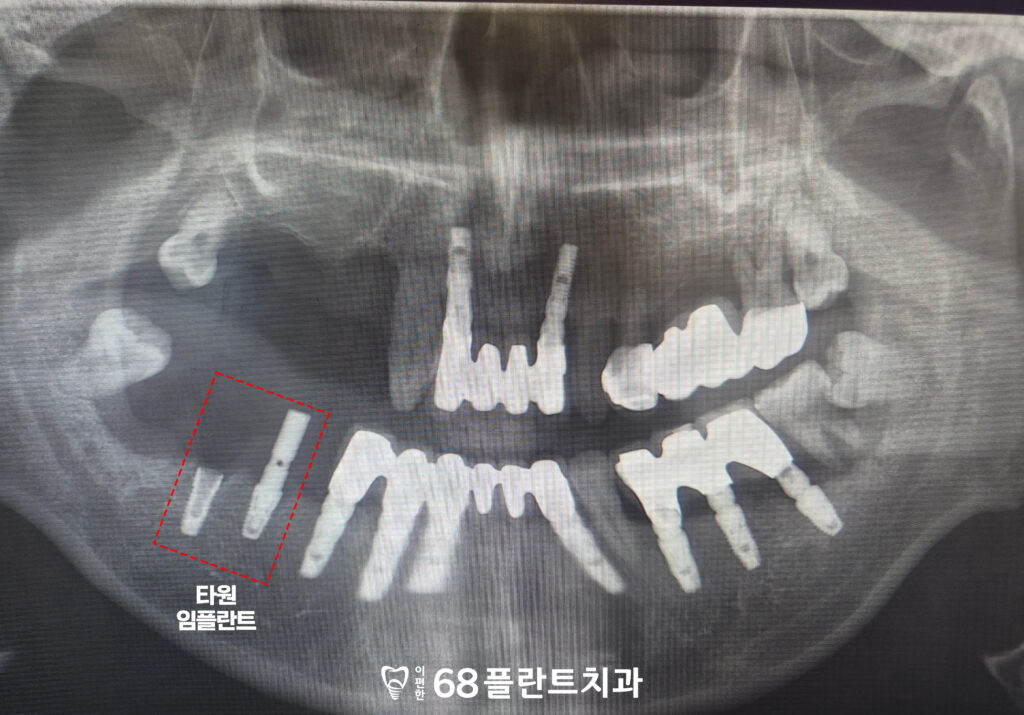

<타원 임플란트 보철>

또한 오른쪽 아래는

타원에서 임플란트를 식립한 후

보철을 이어서 진행하지 않은 상태로,

임플란트가 기능하지 못한 채 방치되어 있었습니다.

이로 인해 저작 기능이 제대로 이루어지지 않았으며,

주변 치아에도 부담이 가해지고 있는 상황이었습니다.

따라서 해당 부위는 임플란트 상태를 면밀히 평가한 후

보철 치료를 통해 정상적인 기능을 회복할 수 있도록

치료 계획을 함께 수립하였습니다.